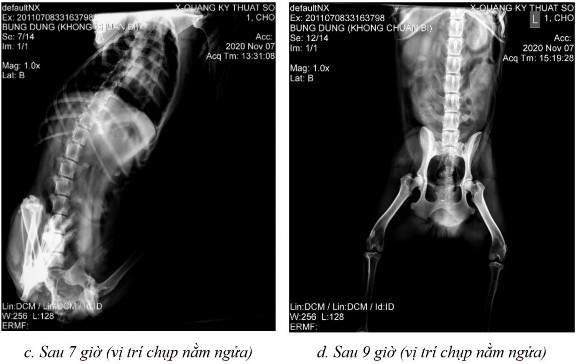

Phụ lục 5.2. Hình ảnh X-quang chó 3 ở thời điểm (a) sau 2 giờ 15 ở vị trí nằm ngửa, (b) sau 4 giờ ở vị trí nằm ngửa, (c) sau 7 giờ ở vị trí nằm ngửa và (d) sau 9 giờ ở vị trí nằm ngửa